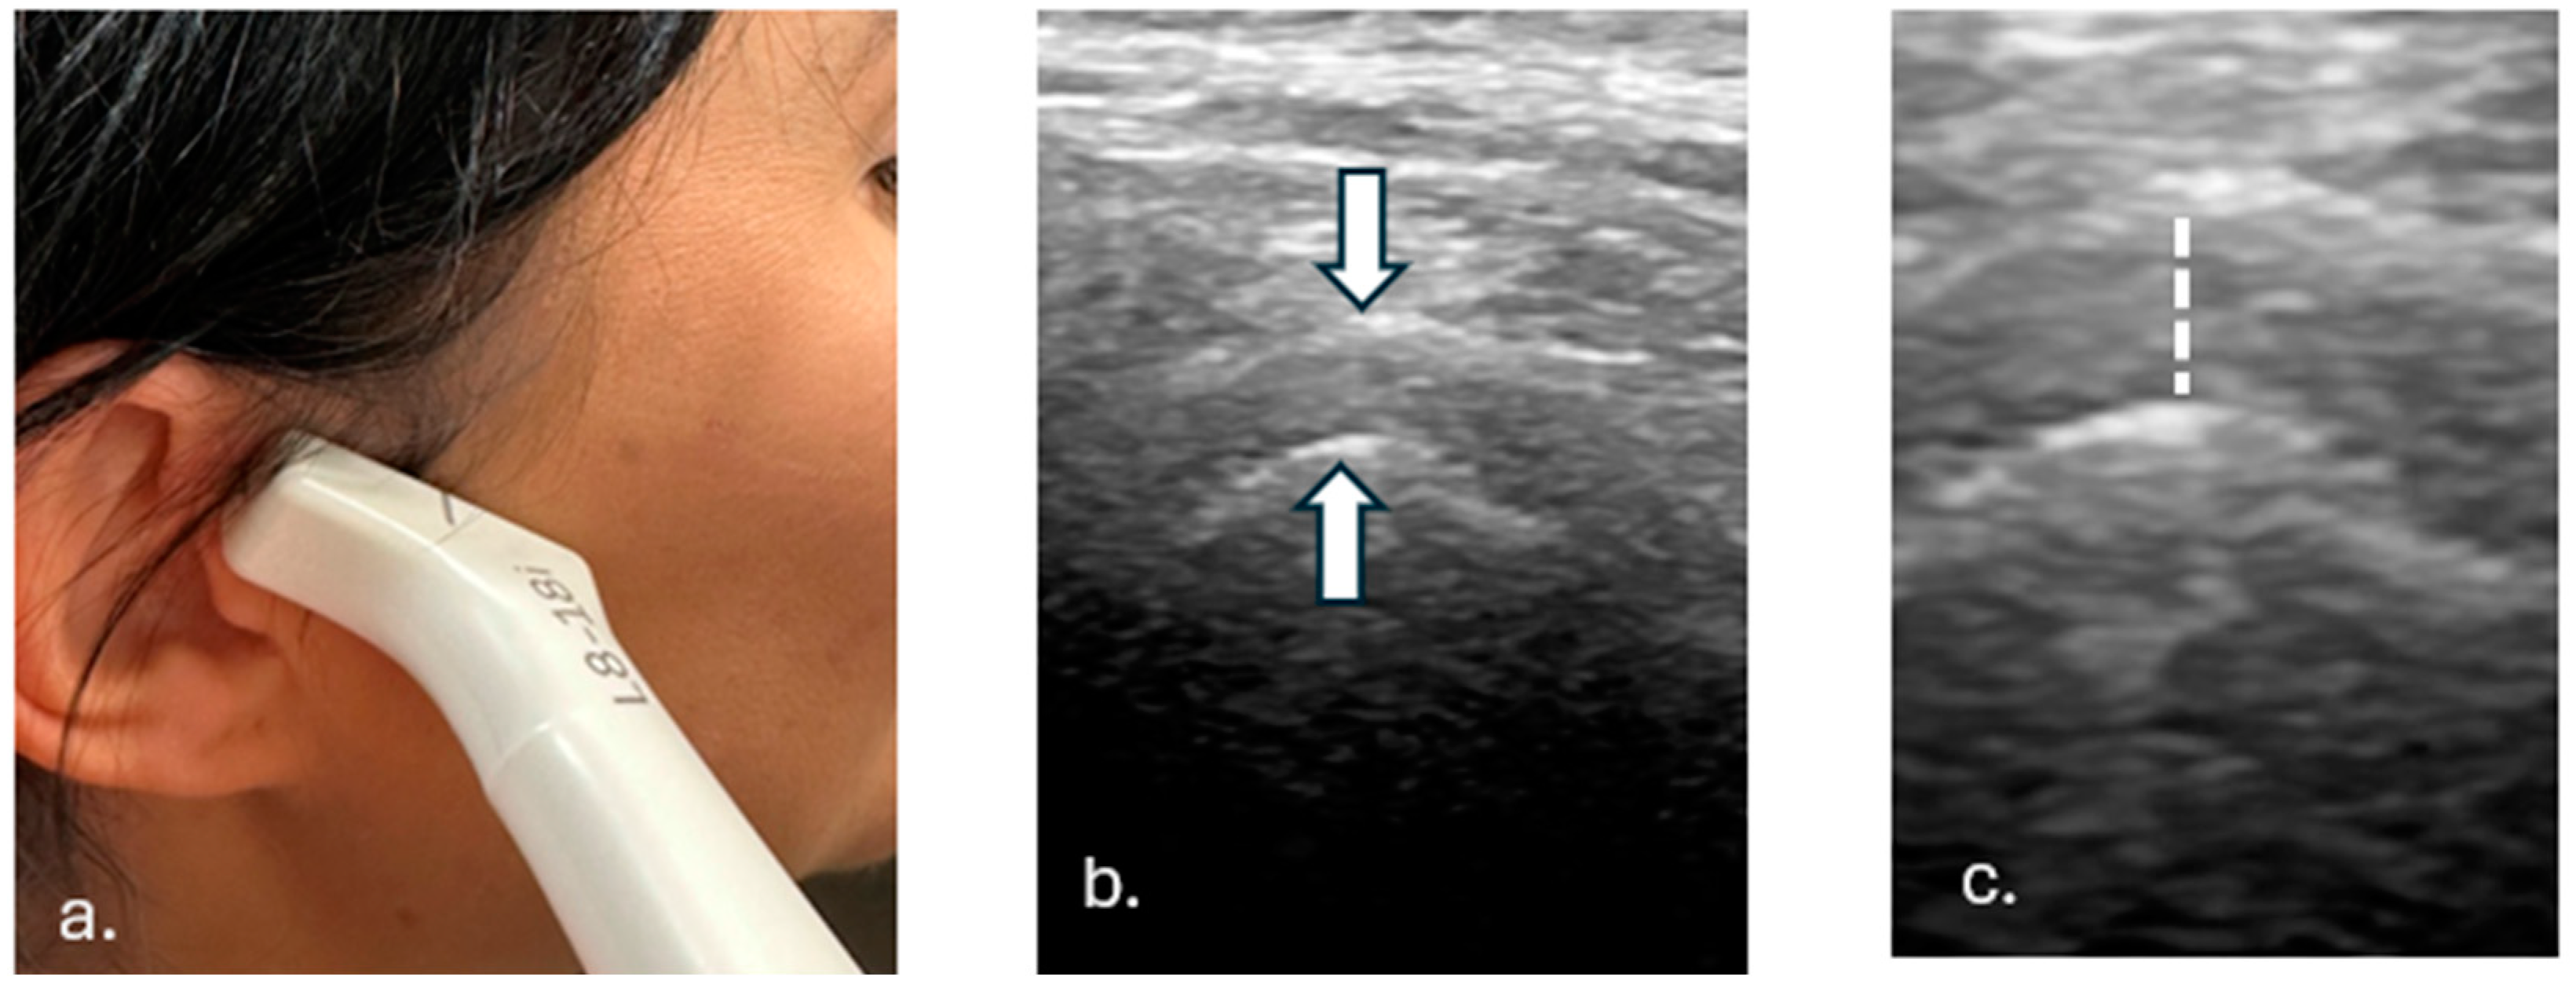

2.2. Examination Protocol